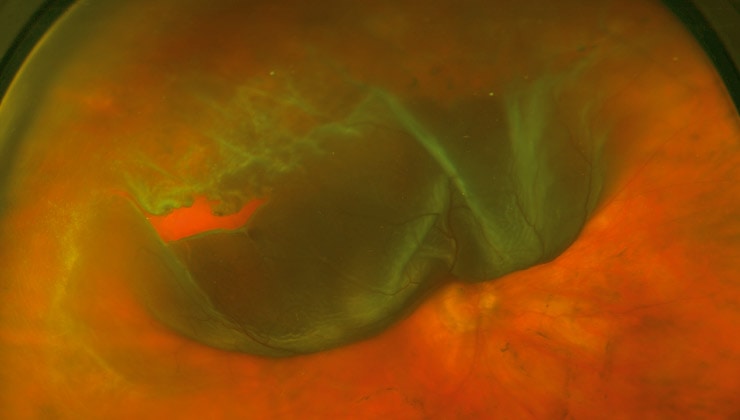

La cirugía combinada del desprendimiento de retina, uniendo la técnica escleral a la vitrectomía, aumenta hasta un 10% la tasa de éxito del tratamiento quirúrgico de esta enfermedad. Así lo han expuesto especialistas de IMO en el World Ophthalmology Congress (WOC 2018), la principal cita de la oftalmología celebrada en Barcelona con la participación de profesionales de más de un centenar de países.

Como explica el Dr. José García-Arumí, especialista del Departamento de Retina y Vítreo de IMO y ponente de la sesión de “Controversias quirúrgicas en el desprendimiento de retina” del WOC, “aunque una vitrectomía bien practicada ya logra muy buenos resultados por sí misma, estudios realizados y nuestra propia experiencia demuestran que reforzar la intervención con cirugía escleral permite fijar la retina en su sitio pasando de un 85% a un 95% de eficacia”. En consecuencia, se reduce el riesgo de que vuelva a producirse un nuevo desprendimiento, algo que, sin una correcta indicación y ejecución de la técnica inicial, puede afectar a cerca de la mitad de los pacientes operados, precisando una segunda, una tercera e, incluso, una cuarta operación.

Según el oftalmólogo de IMO, “la realización conjunta de la vitrectomía y la cirugía escleral está especialmente indicada para casos difíciles: desprendimientos de retina con múltiples agujeros, con desgarros gigantes, en ojos previamente intervenidos de catarata o asociados a proliferación vitreorretiniana (membrana que se forma sobre la retina y aumenta su rigidez en pacientes operados varias veces, con mucha inflamación o en niños)”.

La vitrectomía y la cirugía escleral son dos técnicas que pueden utilizarse para tratar el desprendimiento de retina y que pueden realizarse tanto de forma combinada como separada.

El procedimiento consiste en poner un “cinturón” alrededor del ojo, sujetándolo a su pared más externa (la esclera), donde normalmente se producen las roturas retinianas. Además de combinarse con la vitrectomía –que se basa en extraer el gel vítreo que rellena el globo ocular y que, por diferentes causas, puede traccionar la retina y desprenderla–, la cirugía escleral también se realiza de forma aislada. Al rodear el ojo con una banda o anillo de silicona, este se comprime y se alivia la tensión que tira de la retina, a la que está adherido el vítreo.